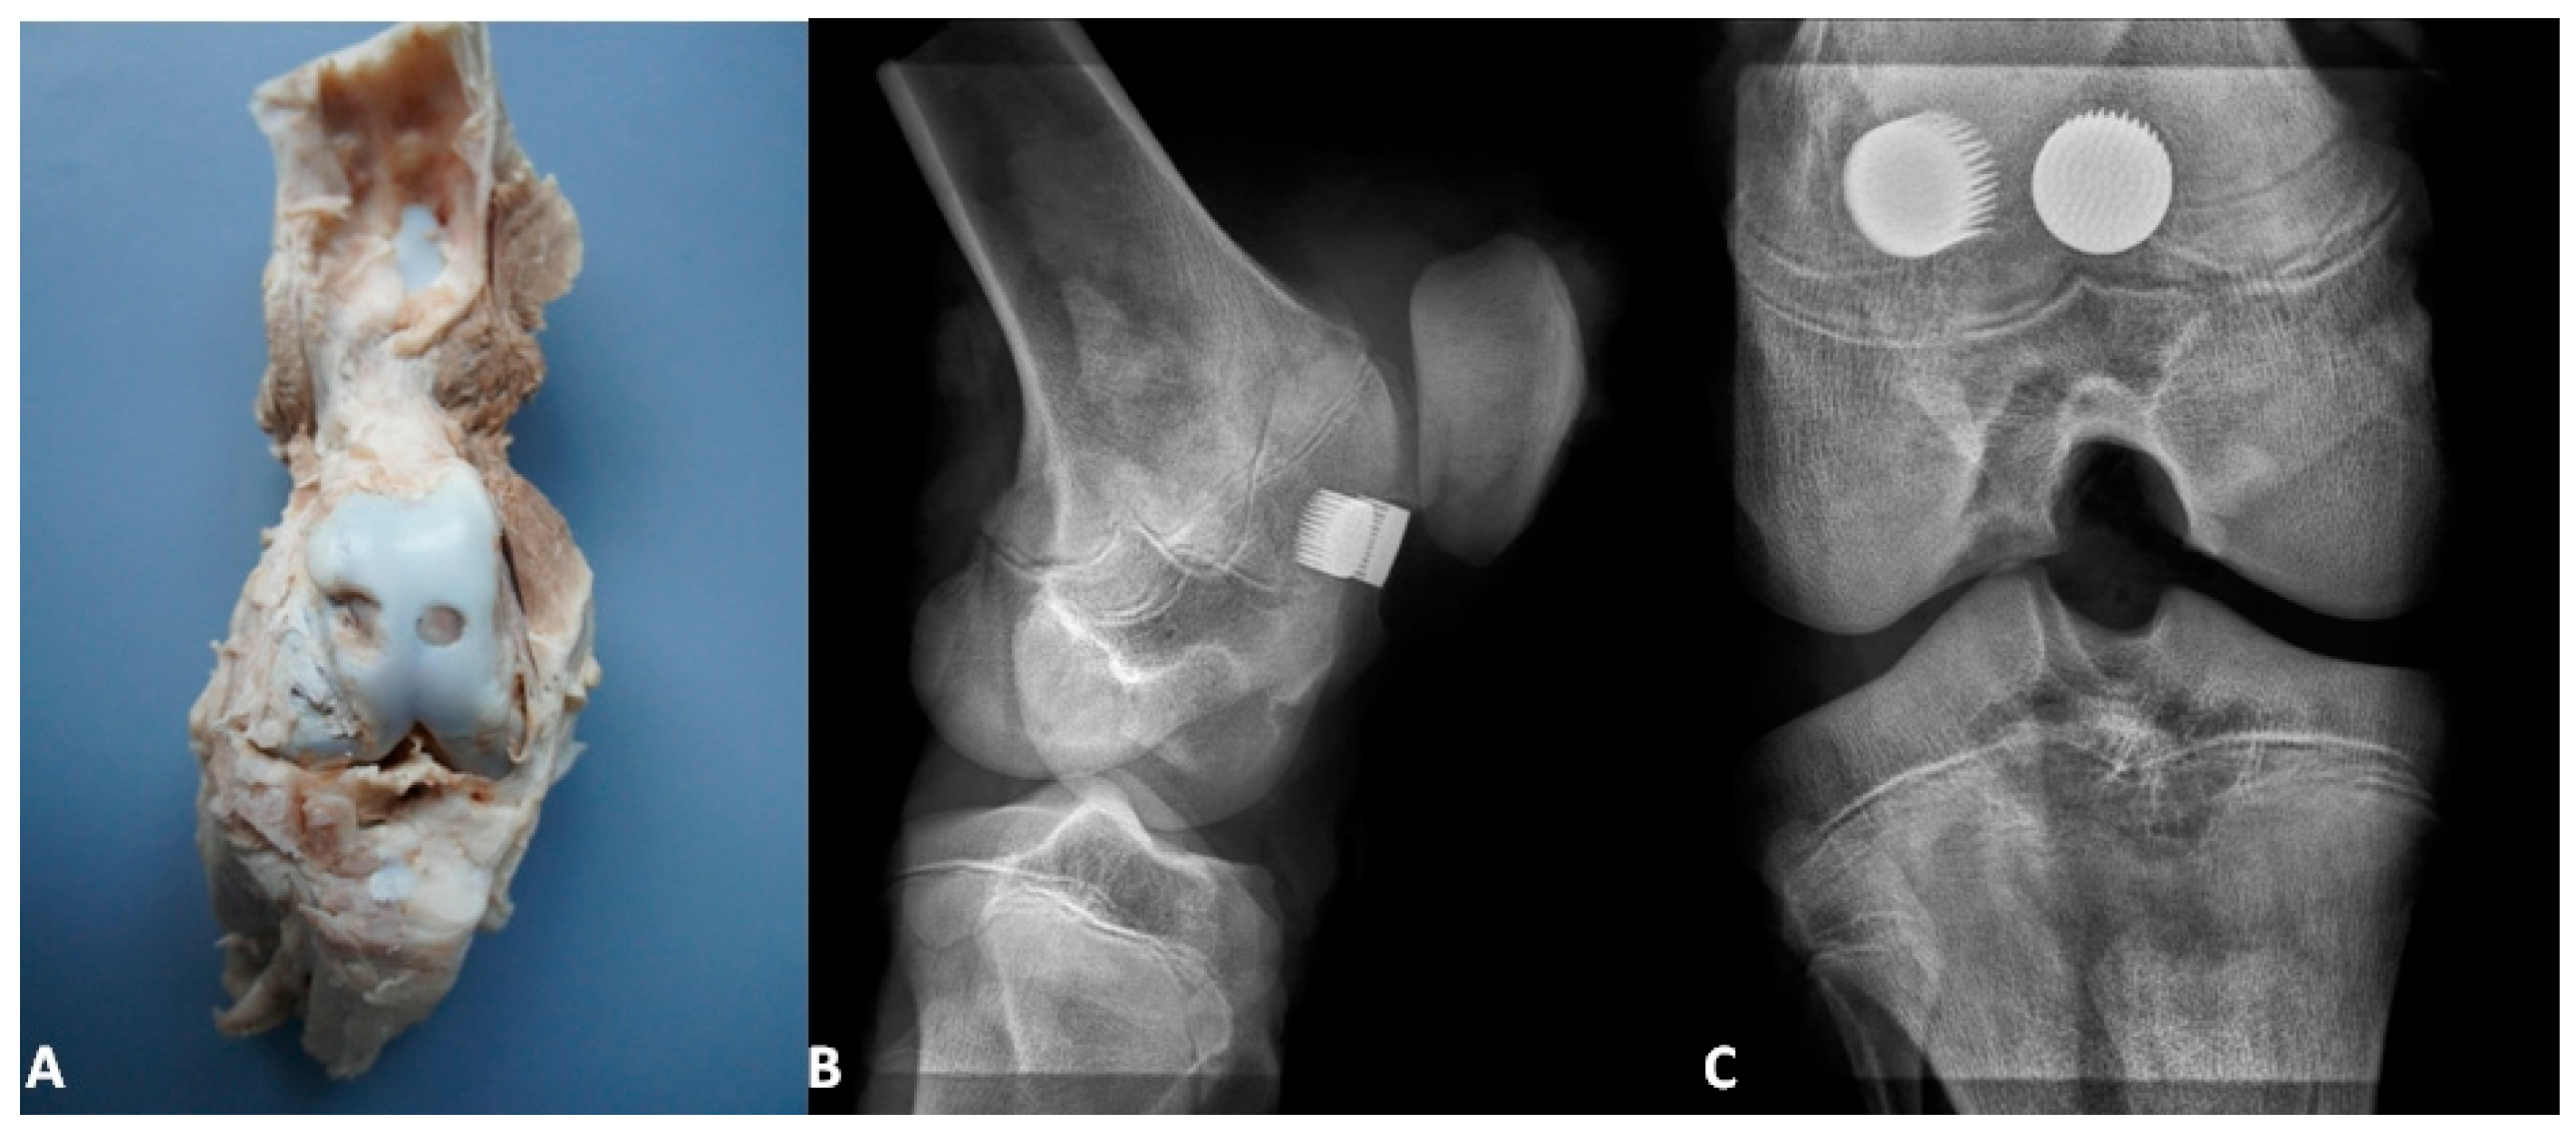

Figure 3, Figure 4 and Figure 5 present the exemplary results of the experimental study of biointegration of unmodified and Ca-P surface-modified PSc350 MSC-Scaffold prototypes conducted in an animal model. In Figure 3A the specimen of the operated swine knee joint with the implanted two preprototypes of the MSC-Scaffold resected surgically at eightweeks after the implantation is presented. In the surgically-explanted knee joint no femoral condyle destruction was observed. the two implanted pre-prototypes of the MSC-Scaffold showed good fixation without any signs of loosening. In Figure 3B,C the 2D digital X-ray radiograms (XPERT 40, Kubtec, Milford, CT, USA), respectively, lateral and anteroposterior, of the resected swine knee joint are shown. The radiological examination confirmed very good stability of the knee joint and no implant migration, as well as showed the spaces between spikes of the MSC-Scaffold of the both implanted MSC-Scaffold pre-prototypes filled by bone tissue.

Figure 3. (A) The specimen with the implanted two pre-prototypes of the MSC-Scaffold explanted surgically at eight weeks after the implantation; the lateral (B) and anteroposterior (C) 2D digital X-ray radiograms of the explanted swine knee joint.